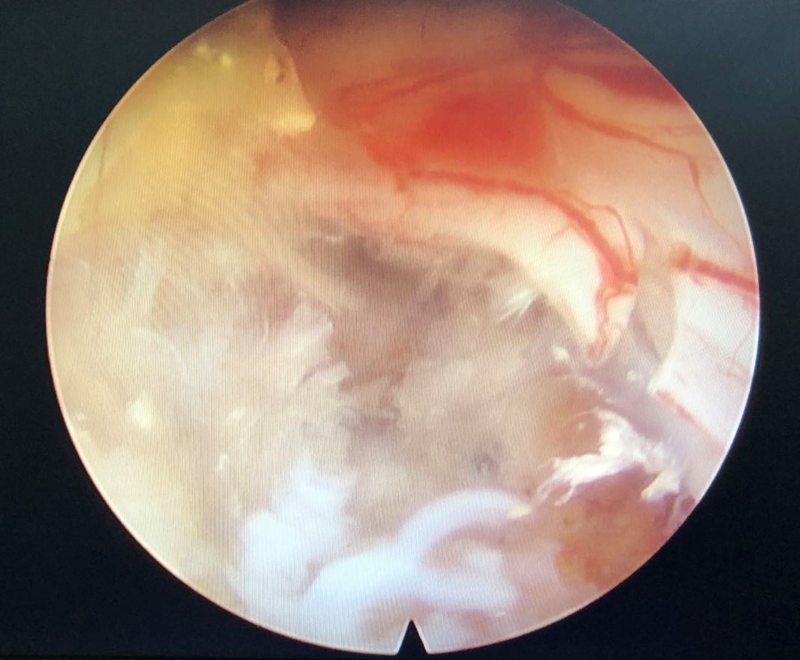

3、硬膜撕裂

硬脊膜撕裂一般由于镜下操作不当产生机械性损伤引起,也可在行椎间孔成形的过程中环锯或磨钻使用,超过椎弓根内缘而损伤硬脊膜。文献报道发生率在1%左右,其大多发生在突出间盘较大、组织黏连较为严重的病例中,其次,也与手术医师暴力操作、手术视野不佳有关。

若怀疑发生硬脊膜撕裂应及时探查,有学者报道有些较小的裂口未行修补硬脊膜可自行愈合,不需特殊处理。若发生比较严重的脑脊液漏应及时明确诊断行开放手术修补,避免发生永久性神经症状。